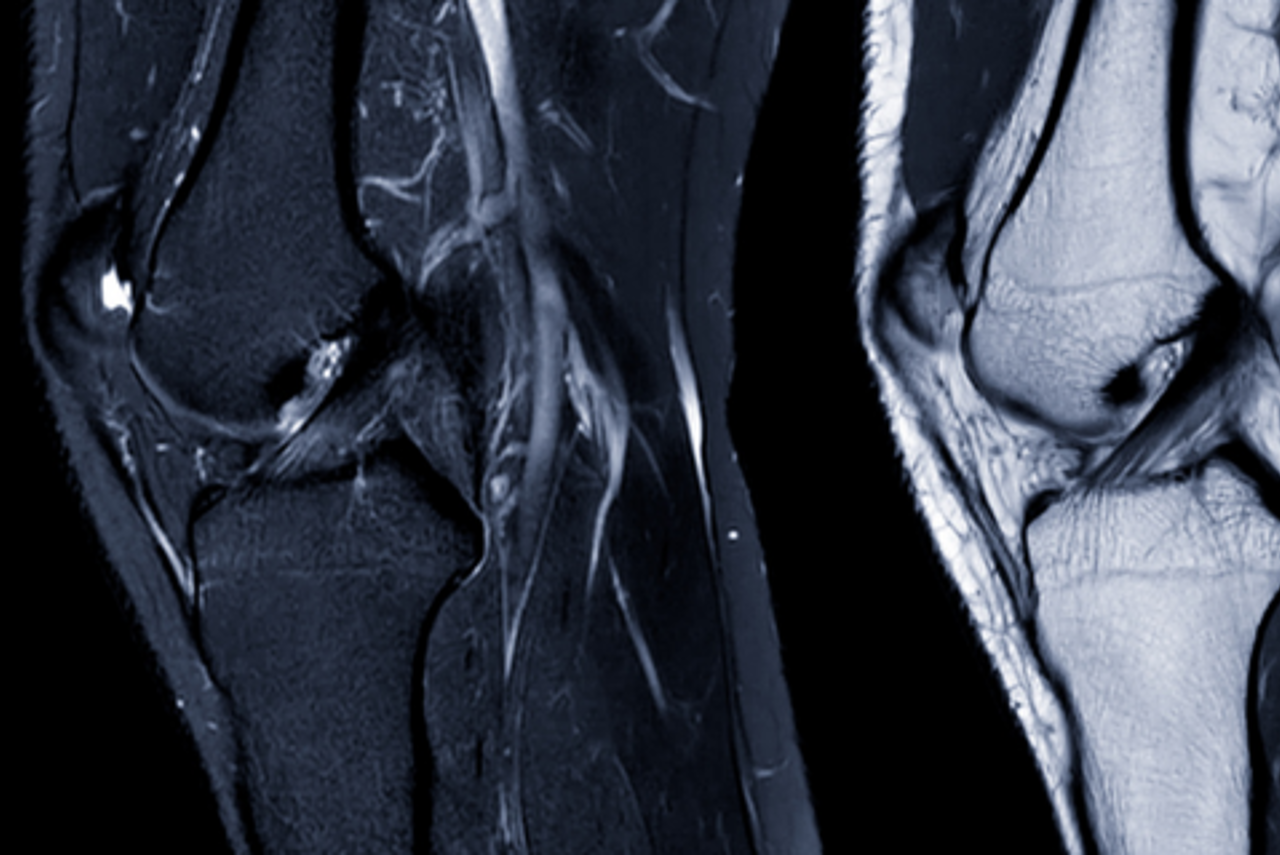

Musculoskeletal MRI FAQs

Musculoskeletal imaging can assess a wide range of medical conditions affecting the spine, shoulder, elbow, wrist, hip, knee, ankle and other joints, and helps provide high-quality images of bones, cartilage, ligaments, tendons, muscles and surrounding soft tissue structures.